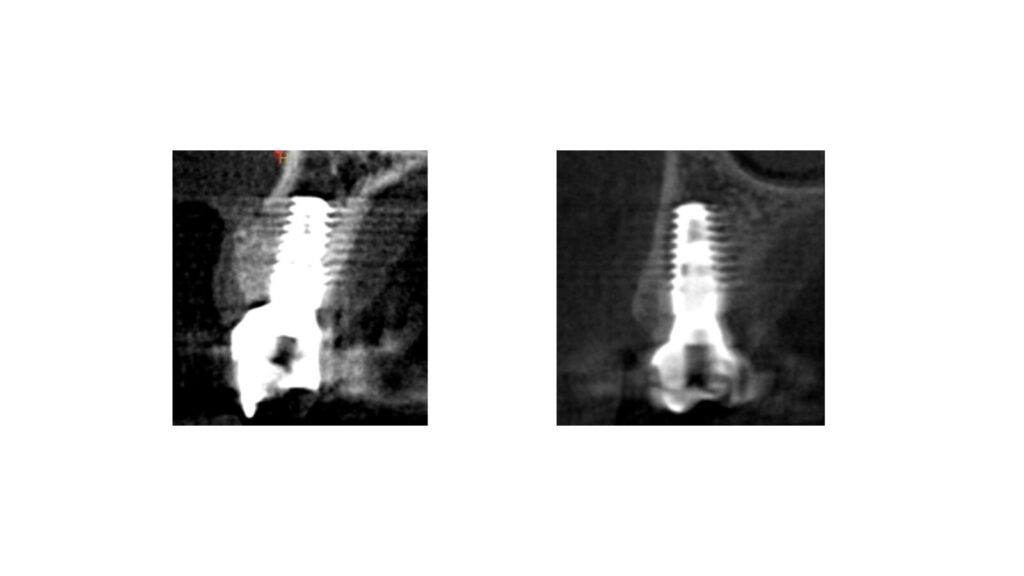

• RUOLO DEL PLATFORM SWITCHING NELLA

ANALISI DEL RIASSORBIMENTO CRESTALE

• VALUTAZIONE DEI PARAMETRI CLINICI E RADIOGRAFICI

• TERAPIA IMPLANTARE DEI SETTORI ANTERIORI

• PROTOCOLLI CHIRURGICI NELL’ INSERIMENTO

DELL’ IMPIANTO POST ESTRATTIVO IMMEDIATO E

DIFFERITO A MEDIO E LUNGO TERMINE